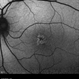

- retinal dystrophy

- Scanning laser ophthalmoscope

- 34 year old male with colour blindness and loss of visual field